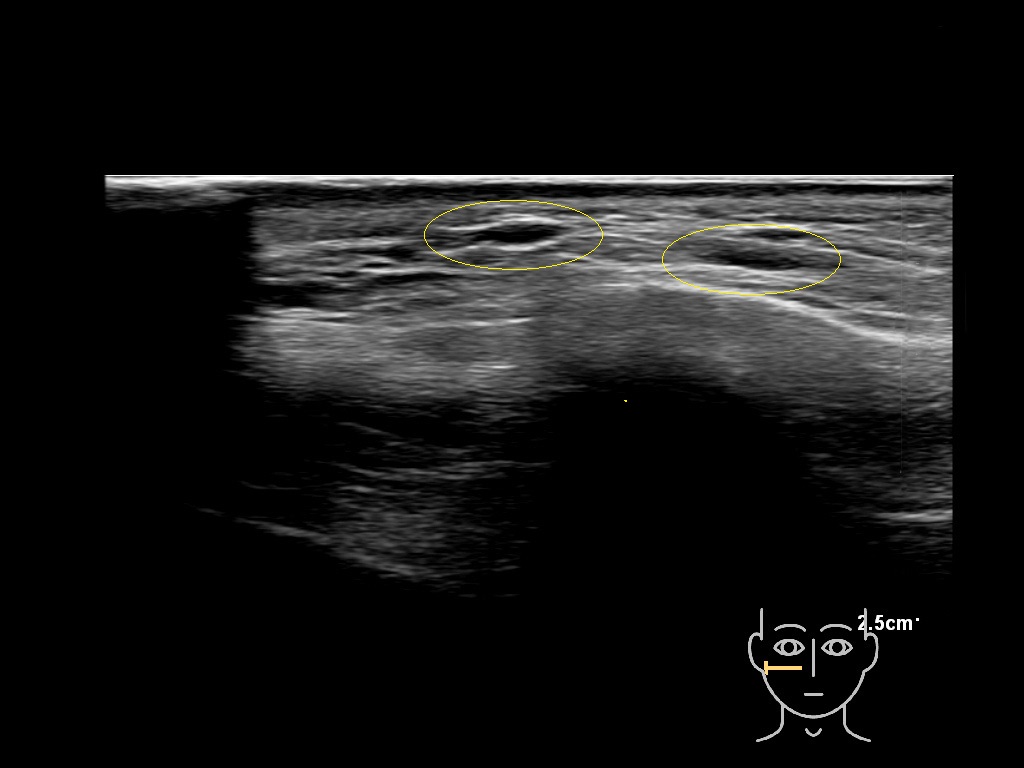

Fascia

Filler deposits may end up unintentionally in the SMAS or fascial layers of the skin. Very often this will not lead to adverse events, however, adverse events ( nodules, migration / redistribution impaired muscle movement and smiling and malar edema) are are often related to filler ending up in the SMAS or fascia.

Hover over an image to view the secondary image or click on the image title for more information.